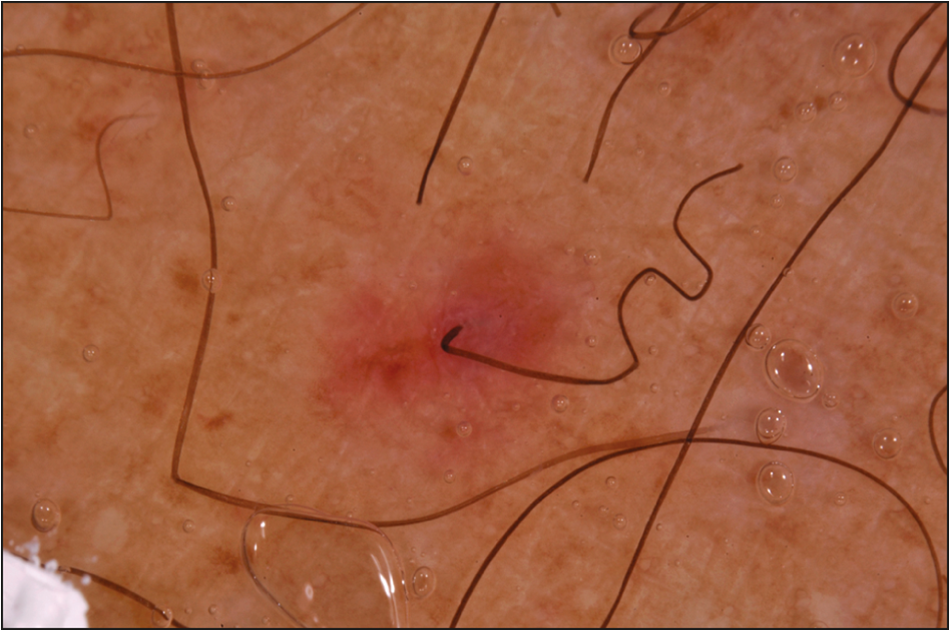

Kluesner, Nicholas and Miller, daniel. “Scurvy: Malnourishment in the land of the plenty.” The journal of emergency medicine. Vol 46. no 4. pages 530-532. 2014.